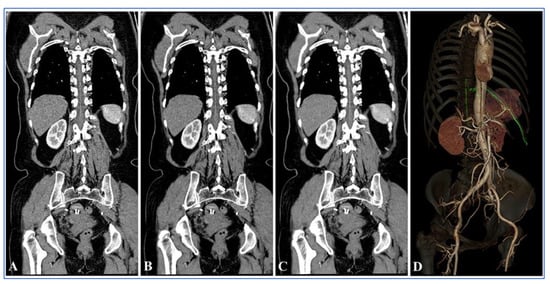

| Groups | Image Reconstruction Methods | Visualization Scores of the Adamkiewicz Arteries | Hairpin Curve | Branching Level | ||||

|---|---|---|---|---|---|---|---|---|

| 1 = Poor | 2 = Fair | 3 = Good | 4 = Fine | 5 = Excellent | ||||

| Group B | 120 kV FBP | 12 (24.0%) | 14 (28.0%) | 11 (22.0%) | 9 (18.0%) | 4 (8.0%) | 38 (76.0%) | 24 (48.0%) |

| Group A | 100 kV FBP | 5 (10.0%) | 9 (18.0%) | 16 (32.0%) | 12 (24.0%) | 8 (16.0%) | 45 (90.0%) | 36 (72.0%) |

| 100 kV ASIR-V 60% | 3 (6.0%) | 5 (10.0%) | 10 (20.0%) | 19 (38.0%) | 13 (26.0%) | 47 (94.0%) | 42 (84.0%) | |

| 100 kV ASIR-V 70% | 3 (6.0%) | 4 (8.0%) | 10 (20.0%) | 20 (40.0%) | 13 (26.0%) | 47 (94.0%) | 43 (86.0%) | |

| 100 kV ASIR-V 80% | 2 (4.0%) | 3 (6.0%) | 9 (18.0%) | 22 (44.0%) | 14 (28.0%) | 48 (96.0%) | 45 (90.0%) | |

| 100 kV ASIR-V 90% | 2 (4.0%) | 3 (6.0%) | 7 (14.0%) | 24 (48.0%) | 14 (28.0%) | 48 (96.0%) | 45 (90.0%) | |

| 100 kV ASIR-V 100% | 2 (4.0%) | 3 (6.0%) | 6 (12.0%) | 24 (48.0%) | 15 (30.0%) | 48 (96.0%) | 45 (90.0%) | |